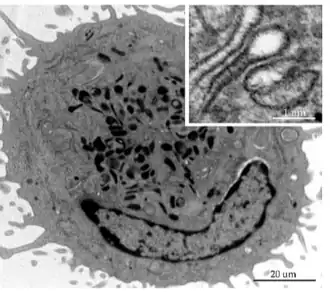

Ultraestructura

Con microscopía electrónica las LC son células de aspecto estrellado, sus finas prolongaciones («dendritas») atraviesan las uniones estrechas hacia el estrato córneo y pueden buscar antígenos en varias capas de la epidermis.[6]

El núcleo es dentado con circunvoluciones o bien lobulado.

El citoplasma es electrolúcido, desprovisto de tonofilamentos y melanosomas.[9]

Inicialmente se identificaron por un marcador citoplasmático específico, el gránulo de Birbeck, un orgánulo denso en electrones.

La célula CL muestra ausencia de desmosomas.[9]

Gránulos de Birbeck

El componente principal de los gránulos de Birbeck es la lectina de membrana de tipo C (CD207) denominada langerina,